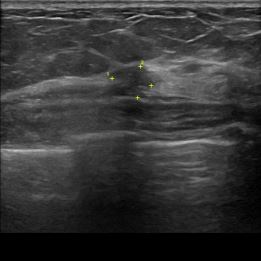

상기환자는 외부검사상 조직검사 권유받고 내원하신 60대 초반

여성분으로 의심스러운 좌측유방혹 조직검사 시행해 유방암으로 진단되었습니다